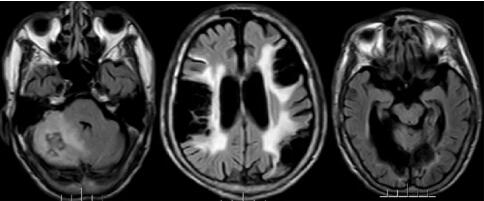

据林先生介绍,林大爷既往有高血压、房颤病史。自2011年以来,曾三次因脑梗住院,并遗留了饮水呛咳、肢体抖动等症状。入院后,我院副院长、神经内科专家王展航为患者完善了相关检查,发现他颅内有新的脑梗部位。为进一步明确病因,王展航又邀请了心理行为医学科专家及康复医学科专家进行会诊。经讨论分析,最终诊断患者为器质性精神障碍、右侧小脑出血性脑梗死(亚急性)及脑梗死后遗症。